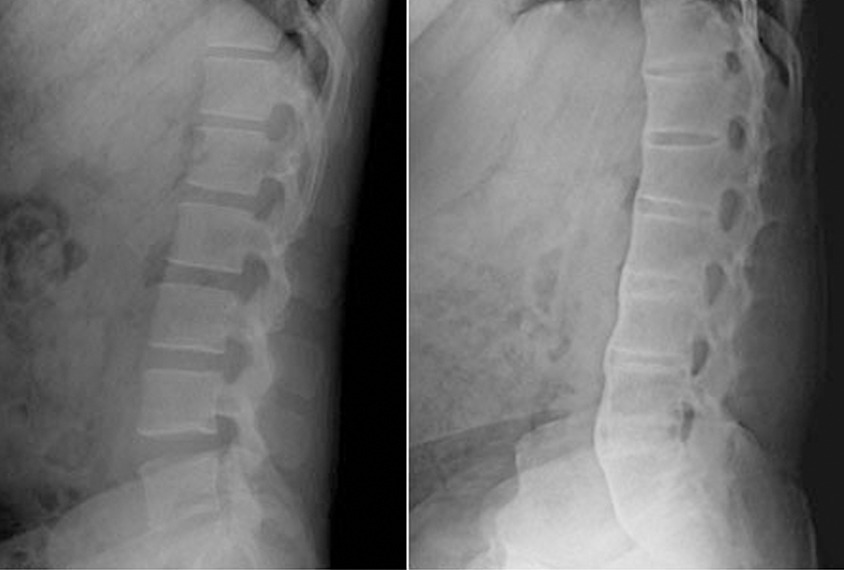

강직성척추염 – 척추 염증과 통증